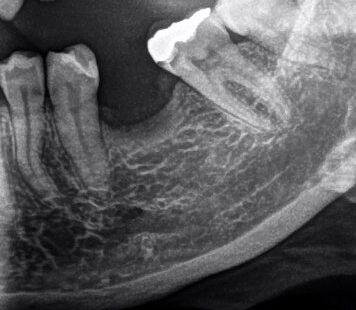

úbytok kostnej hmoty (odborne atrofia kosti, nemá nič spoločné s kostnou dreňou) po vytiahnutí zubu je prirodzeným javom, nakoľko kosť alveolárne výbežku si uchováva svoju výšku vďaka prítomnosti zubov v nej uložených a prenosu žuvacích síl.

Druhá stolička sa vám už začala skláňať do vzniknutej medzery.

Posun zubu, respektíve jeho koreňa s použitím čeľustného aparátu, je možný, avšak nemusí to byť vo vašom prípade najvhodnejšie riešenie. Je potrebný názor špecialistu - čeľustného ortopéda, ktorý zhodnotí celkový stav vášho chrupu, stupeň ústnej hygieny, prihliadne na váš vek a iné faktory.

Čeľustný ortopéd vám tiež bude vedieť povedať, o aký čas sa predĺži liečba hlbokého zhryzu riešením tohto nedostatku. Alternatívou riešenia medzery medzi druhým črenovým zubom a druhou stoličkou by vo vašom prípade bolo zhotovenie mostíka a to aj vzhľadom k tomu, že oba pilierové zuby sú už ošetrené výplňami.